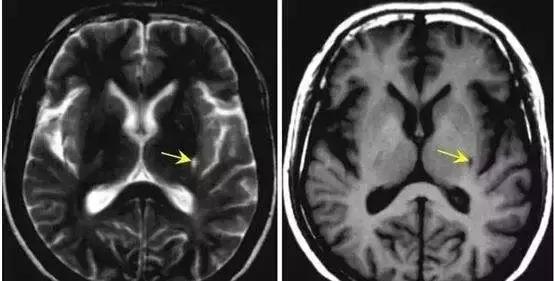

双侧基底节区腔隙灶(腔隙性脑梗塞)

双侧基底节区腔隙灶是CT诊断常用的非规范性术语,主要包括基底节区腔隙性梗死、扩大的血管周围间隙、脉络膜裂囊肿等,这些在CT图像上无法区分时,就会用腔隙灶来诊断。鉴别腔隙灶是生理性的还是病理性的,就要根据患者有无临床症状及体征,必要时还需要头颅磁共振(MR)检查。

|内容拓展(来自彩虹神经内科医生)——腔隙性脑梗死

腔隙性脑梗死,是脑梗死诸多类型中的一种(如果是微小血栓导致的腔隙性脑梗死,属于脑栓塞的概念),是大的脑动脉分出的的单个小穿通支血管闭塞引起的非皮质性小梗死(梗塞灶的直径一般在0.2-15毫米),这个概念最早来自19世纪,当时医生在尸体解剖中发现这类病灶,发现在大脑的中心部位及脑皮质的下面脑干上有很多的体积很小的缺血性的病灶,后来通过CT、磁共振等技术在活体上也得到了证实。不过,随着人们这类疾病认识的不断提高,腔隙性脑梗死这个诊断名词的争议也越来越大,临床应用也越来越少,它更多的被“脑小血管病”等诊断所替代。

至于“腔隙性脑梗死”发病的原因,目前的观点主要包括以下几种:

1. 小的穿通支动脉的小动脉硬化(主要是脂质透明变性)是常见病因,尤其是较小的梗死(长度为3-7毫米)。

2. 源自一些大血管,如大脑中动脉主干、脑底动脉环、基底动脉远端或椎动脉远端的穿通支动脉起始处的微粥样硬化斑。也就是说这些小穿支动脉的开口的地方由于斑块的完全或次全的遮盖,导致缺血。

3. 在某些情况下,虽然未经病理证实,但很多科学家仍怀疑微小栓子是这些小梗死的原因。

腔隙性脑梗死占所有的缺血性脑卒中(包括脑梗死和脑栓塞等)的15%-26%。

上面描述的三种腔隙性脑梗死病因中有两种与高血压相关性慢性血管病变有关。其他,如吸烟、糖尿病等因素也被认为参与其中。

Fig 4 脑内腔隙灶